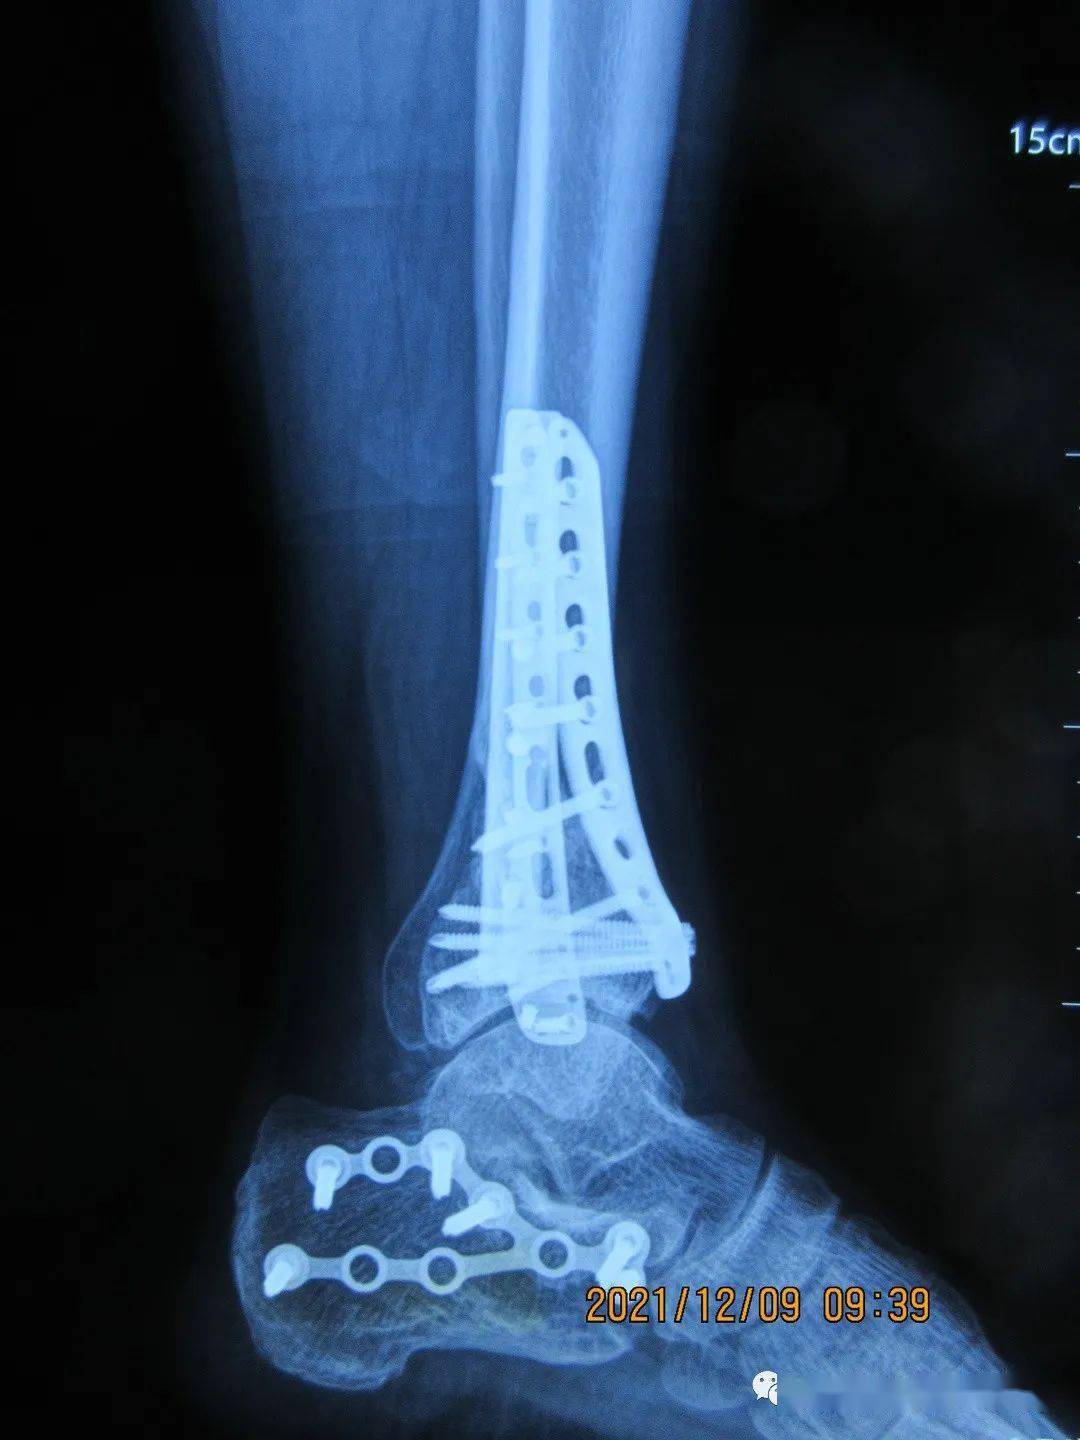

病例2:高空坠地,双侧踝关节骨折